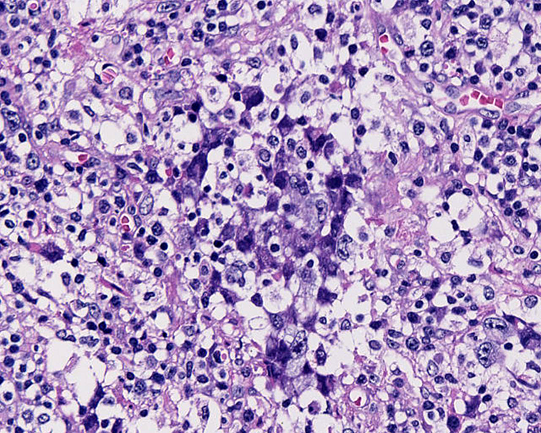

20歳 鼠径リンパ節

左臀部の痛みで発症する。臀部軟部組織に腫瘤を認めCTで腸骨, 大腿骨の欠損あり。左鼠径, 大動脈周囲, 後腹膜, 骨盤内腔のリンパ節が腫大し脾腫、胸水腹水の貯留を認める。WBC 15500/cmm, LDH 470(<350), sIL2-R29100U/ml

リンパ節組織所見

大型異型細胞が集簇し結合性に増殖している。未分化癌や悪性黒色腫が鑑別となる。細胞は大型で類円形, 楕円形核に加えて腎臓様の特異な核形を示す。

免疫染色:CD3-, CD4-, CD8-, CD15-, CD20-, CD30+, CD43-, CD45RO-, CD56-, TIA1+, granzymeB+, ALK+, EMA+, EBER-ISH-, LMP1-, BCL2- (以上, consultation先で染色)

Pathological Diagnosis: ALK-positive anaplastic large cell lymphoma